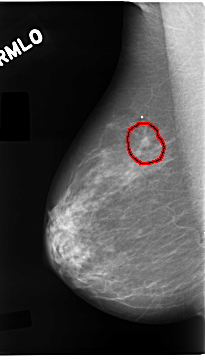

C_0096_1.RIGHT_MLO

FILE: C_0096_1.RIGHT_MLO.OVERLAY

TOTAL_ABNORMALITIES 1

ABNORMALITY 1

LESION_TYPE CALCIFICATION TYPE PLEOMORPHIC DISTRIBUTION CLUSTERED

LESION_TYPE MASS SHAPE IRREGULAR MARGINS SPICULATED

ASSESSMENT 5

SUBTLETY 5

PATHOLOGY MALIGNANT

TOTAL_OUTLINES 1

BOUNDARY